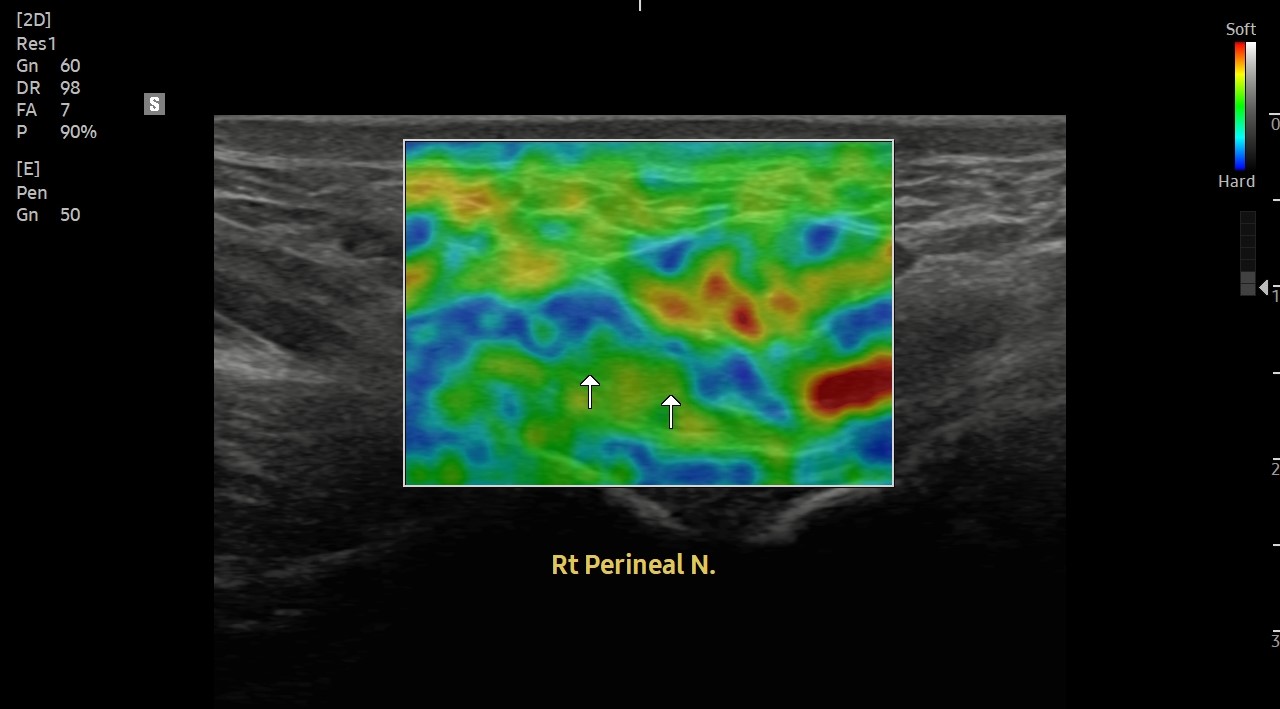

[치료 전]

[치료 후]

- 치료횟수 : 58 회